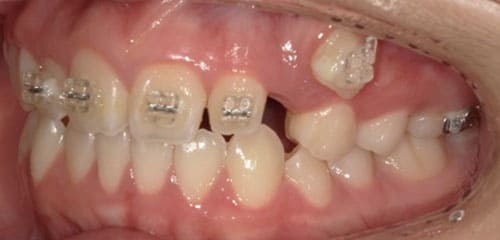

● 歯根が折れ保存不可の歯を抜歯して、そのスペースに八重歯を並べた症例

藤沢デンタルオフィスの虫歯や破折で抜歯後の部分矯正